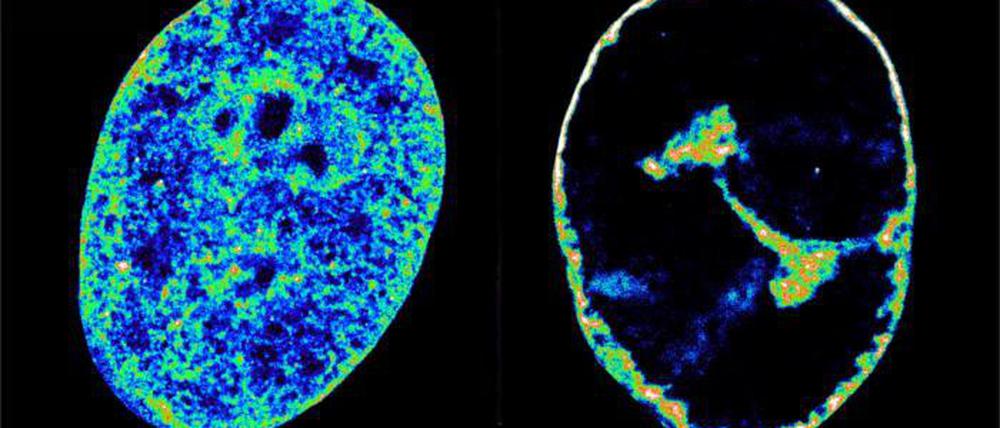

Das Herpesvirus baut sich das Genom menschlicher Zellen gezielt für seine Zwecke um. Binnen kurzer Zeit werde das Erbgut verdichtet und an den Rand des Zellkerns gedrängt, um Platz für die Fabriken zur Virusproduktion zu schaffen, berichtet ein Forschungsteam im Fachjournal „Nature Communications“.